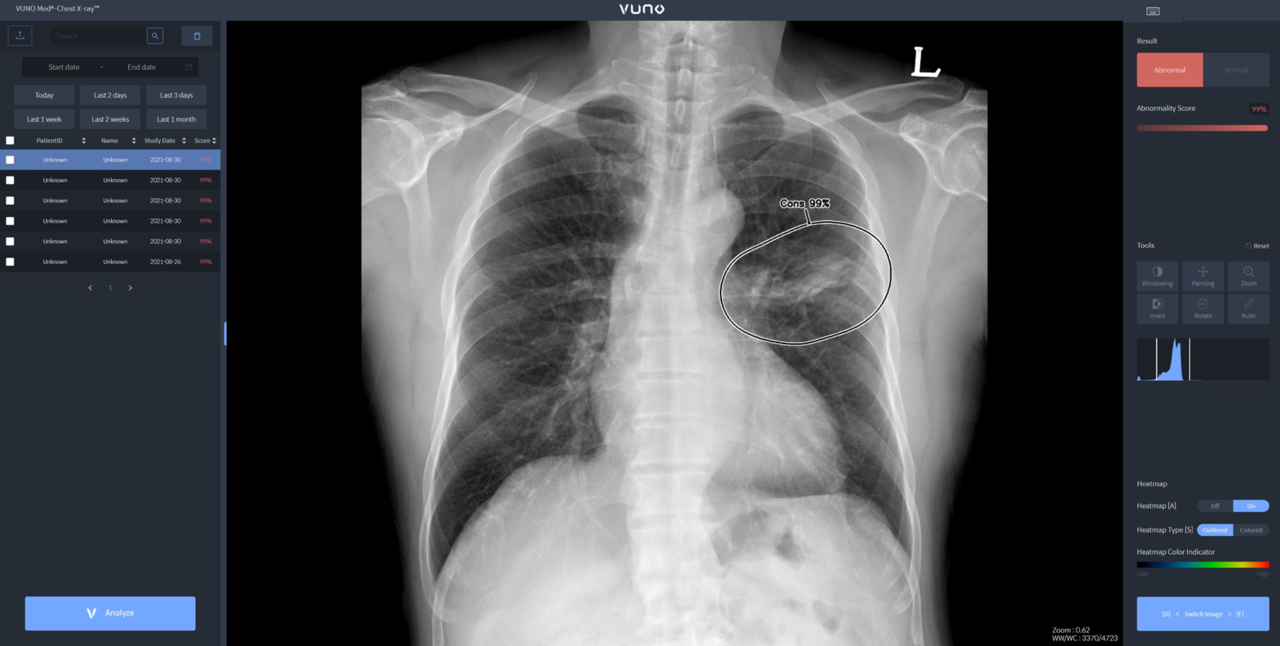

뷰노메드 체스트 X-레이는 흉부 X-레이 영상에서 결절, 경화, 간질성 음영, 흉수, 기흉 등 주요 이상소견을 높은 정확도로 탐지하는 AI 솔루션이다. 의료진에게 이상소견의 소견명과 위치를 제시해 결핵, 폐렴 등 주요 폐 질환 진단을 돕는다. 경량 모델로 개발해 다양한 X-레이 장비에 쉽게 연동할 수 있는 것이 특징이다.

별도 차폐 시설 없이 다양한 상황에서도 쉽게 환자의 흉부 X-레이 촬영을 할 수 있도록 이동형 장비에 연동, 수초 이내에 판독 결과를 확인할 수 있다는 설명이다.